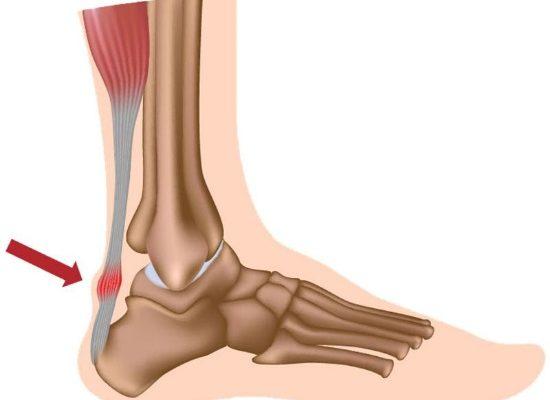

There are two types of Achilles tendinitis, based on which part of the tendon is inflamed. The two types can occur separately or at the same time.

Noninsertional Achilles Tendinitis

In noninsertional Achilles tendinitis, fibers in the middle portion of the tendon (above where it attaches to the heel) are affected. Over time, the fibers may begin to break down and develop tiny tears. This can lead to tendon swelling and thickening.

Insertional Achilles Tendinitis

Insertional Achilles tendinitis involves the lower portion of the tendon, where it attaches (inserts) to the heel bone (also known as the calcaneus).

In both noninsertional and insertional Achilles tendinitis, damaged tendon fibers may calcify (harden) over time. Bone spurs often form on the heel with insertional Achilles tendinitis.